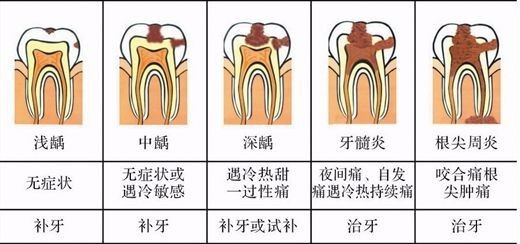

龋齿的分类:根据病变深度可分为浅龋、中龋、深龋。

①浅龋:病变限于牙釉质或牙骨质,患者一般无主观症状。

②中龋:病变已达牙本质浅层,明显龋洞。患者遇冷热酸甜较敏感,但去除刺激因素后症状立即消失。

③深龋:病变已达牙本质深层,一般表现为大而深的龋洞。对外界刺激反应较中龋为重,但刺激源去除后,仍可立即止痛,无自发性痛。